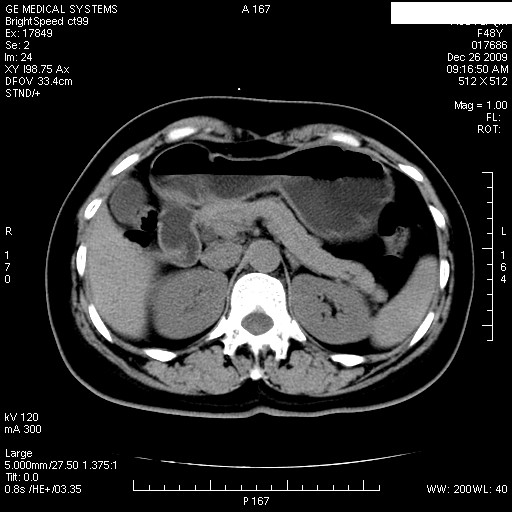

经过抗炎解痉镇痛治疗一周后复查ct如下:

1.图像看上去不是同一人(前组图像十二指肠未见明显异常,后组图像可见十二指肠占位)

2.后组图象印像

a.十二指肠球部前壁占位

b.坏蛆性胆囊炎,胆囊-结肠瘘(瘘口微小且时间较短,结肠内容返流入胆囊,形成胆囊壁钙化,胆囊内钙盐等沉积)

c.胆管炎,肝外胆管轻度扩张

坏蛆性胆囊炎,胆囊-结肠瘘,胆囊内钙盐等沉积.

1)肝内外胆管扩张,原因待查。2)胆囊内药物沉积?